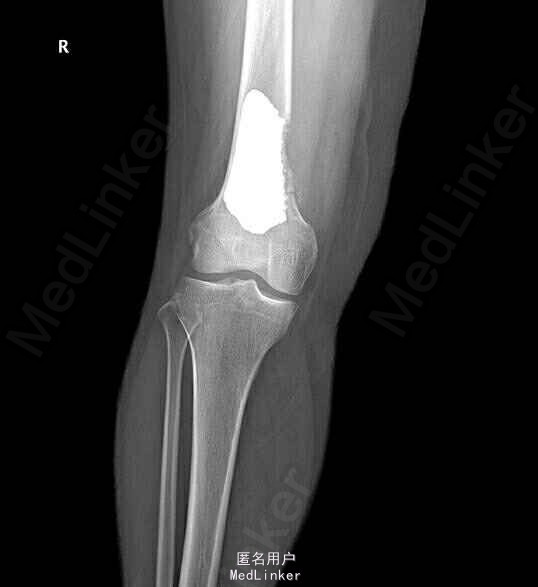

诊断右股骨占位 行右股骨下段占位开窗刮除、骨水泥重建术